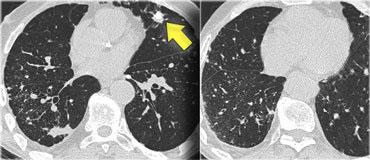

Bên trái là một hình ảnh điển hình khác của sarcoidosis với hạch to trung thất và các nốt nhỏ phân bố theo đường bạch huyết dọc theo bó mạch phế quản và dọc theo các khe liên thùy (mũi tên vàng).

Luôn tìm kiếm các nốt nhỏ dọc theo các khe liên thùy, vì đây là dấu hiệu rất đặc hiệu và điển hình của sarcoidosis.

Hình ảnh điển hình của sarcoidosis với hạch to rốn phổi và các nốt nhỏ dọc theo bó mạch phế quản (mũi tên vàng) và dọc theo các khe liên thùy (mũi tên đỏ).

Hình ảnh chi tiết với biểu hiện HRCT điển hình gồm các nốt dọc theo bó mạch phế quản (mũi tên đỏ) và các khe liên thùy (mũi tên vàng).

Đây là phân bố theo đường bạch huyết điển hình của các nốt.